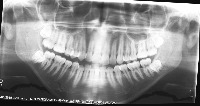

downloadClasses (32)

tooth_11

tooth_12

tooth_13

tooth_14

tooth_15

tooth_16

tooth_17

tooth_18

tooth_21

tooth_22

tooth_23

tooth_24

tooth_25

tooth_26

tooth_27

tooth_28

tooth_31

tooth_32

tooth_33

tooth_34

tooth_35

tooth_36

tooth_37

tooth_38

tooth_41

tooth_42

tooth_43

tooth_44

tooth_45

tooth_46

tooth_47

tooth_48